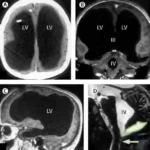

Todo comenzó cuando el hombre acudió al médico por un dolor en la pierna. Lo que reveló la resonancia magnética dejó a los neurólogos sin palabras: la mayor parte de su cráneo estaba llena de líquido, no de materia cerebral.

Inicialmente se pensó que el tejido cerebral se había erosionado. Sin embargo, los expertos ahora creen que su cerebro fue comprimido lentamente por una acumulación de líquido a lo largo del tiempo, producto de una condición llamada hidrocefalia.

El paciente fue tratado en la infancia con una válvula de derivación para drenar el líquido, la cual fue retirada a los 14 años. Desde entonces, el líquido volvió a acumularse silenciosamente, dejando solo una delgada capa de tejido cerebral pegada al interior del cráneo.

Lo increíble es que, a pesar de esto, el hombre vive una vida completamente funcional: está casado, tiene dos hijos, trabaja y solo presenta una leve discapacidad intelectual, con un coeficiente intelectual de 75.